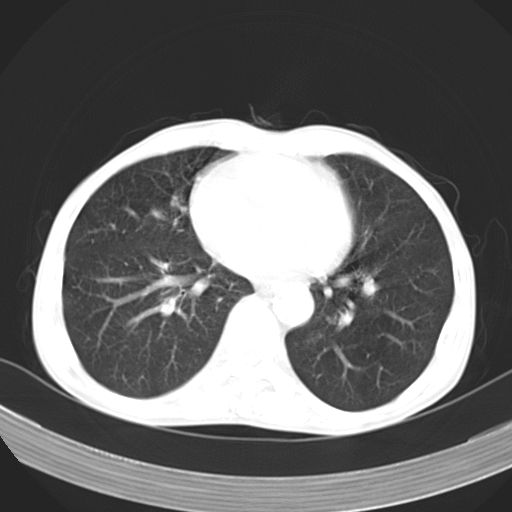

以下是引用苯小孩在2007-5-24 12:47:00的发言:[br]右侧肺门处不均匀密度软组织块影,远端肺组织见斑片模糊影,纵隔内淋巴结明显肿大,边界不清.<纵隔窗第12层面支气管内似见软组织结节>[br]考虑:1、右侧中央性肺癌并阻塞性肺炎并纵隔淋巴结转移可能性大.建议强化或纤支镜进一步检查.[br]2、隆突下淋巴结肿大/食道病变?请做鉴别检查.

以下是引用jw-830在2007-5-24 15:24:00的发言:[br][br] [br] 考虑右肺中央型肺癌并阻塞性炎症,右肺门及纵隔淋巴结转移。 [br] [br][br]